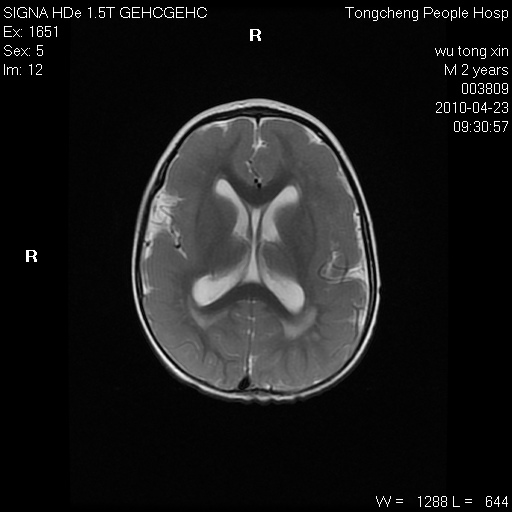

以下是引用赵物学在2010-4-25 12:43:00的发言:[br]巨脑回[br]侧脑室后角低密度影考虑hie或肾上腺脑白质营养不良?[br][br][本贴已被 赵物学 于 2010-4-25 12:51:28 修改过]

以下是引用gaoxiao在2010-4-25 16:54:00的发言:[br]巨脑回畸形。脑白质髓鞘化不良

以下是引用pujunzhi在2010-4-25 21:35:00的发言:[br]考虑 1双侧大脑皮质发育不良 2轻度脑积水 3双侧脑室后角旁片状长t1长t2信号,需继续观察,因为正常小儿此处脑白质的髓鞘化时间可以延迟到4-6岁,才显示正常。